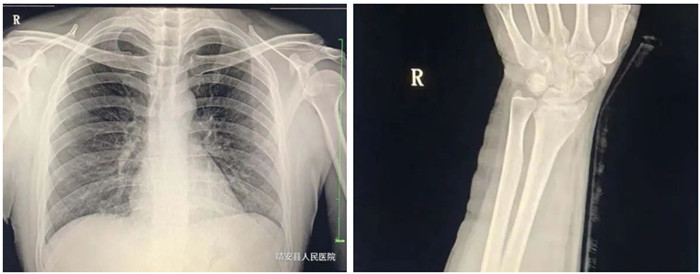

適應(yīng)癥:骨齡檢查、先天性發(fā)育異常、骨缺血性壞死;骨質(zhì)疏松、骨髓炎、骨腫瘤、骨關(guān)節(jié)創(chuàng)傷、骨關(guān)節(jié)結(jié)核、骨關(guān)節(jié)炎性病變、軟組織病變等疾病。

3.胸部

適應(yīng)癥:氣管支氣管病(支氣管結(jié)石及異物等);肺部病變(先天性發(fā)育異常、炎癥、結(jié)核、腫瘤等);縱膈病變(氣腫、血腫、腫瘤與囊腫等)。

普愛醫(yī)療PLX8500D數(shù)字化醫(yī)用X射線攝影系統(tǒng)(動(dòng)態(tài)DR)具有動(dòng)態(tài)、靜態(tài)圖像采集兩種攝影方式。17*17動(dòng)態(tài)大平板,900W高清像素,可以更有效覆蓋檢查范圍、降低檢查所需時(shí)間和曝光,從而確保提升影像檢查效率,有效避免廢片、漏診、誤診、二次拍攝、多次重復(fù)曝光等不良隱患情況的發(fā)生。采用超寬34寸液晶顯示器,解放雙屏雙工作站的束搏,實(shí)現(xiàn)采集圖像和回放圖像并列顯示,使臨床圖像效果對(duì)比更直觀,操作更方便快捷。